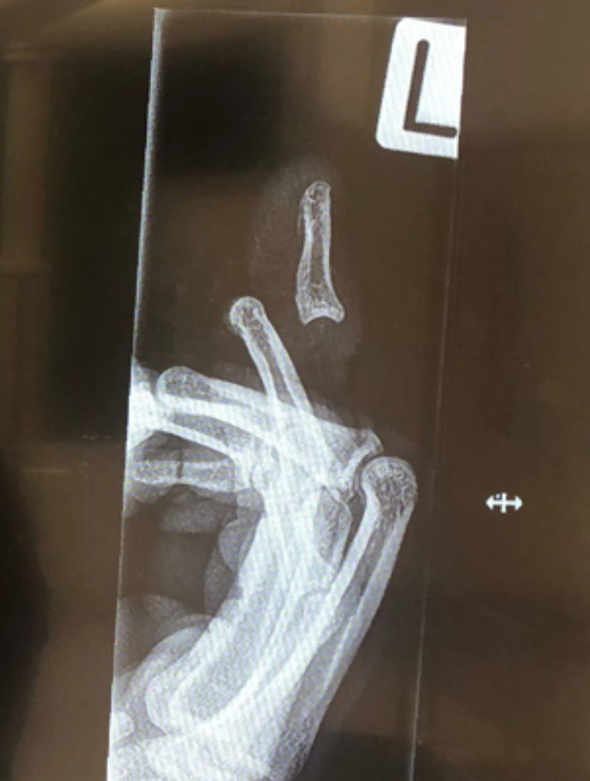

Звезда крикета Джимми Нишам получил ужасную травму пальца во время матча регулярного чемпионата Новой Зеландии.

Спортсмен опубликовал фотографию пальца в Instagram, но травма оказалась настолько серьезной, что социальная сеть была вынуждена разместить на картинке предупреждение о "конфиденциальном контенте".

Впрочем, после перенесенной операции палец, по словам Нимаша, стал "как новенький". Спортсмен надеется вернуться к тренировкам в ближайшее время.

"Мне провели небольшую процедуру, чтобы убедиться, что мой палец все еще в хорошей форме. К счастью, все хорошо. Моя цель - вернуться в строй в начале февраля", - сказал Нишам.